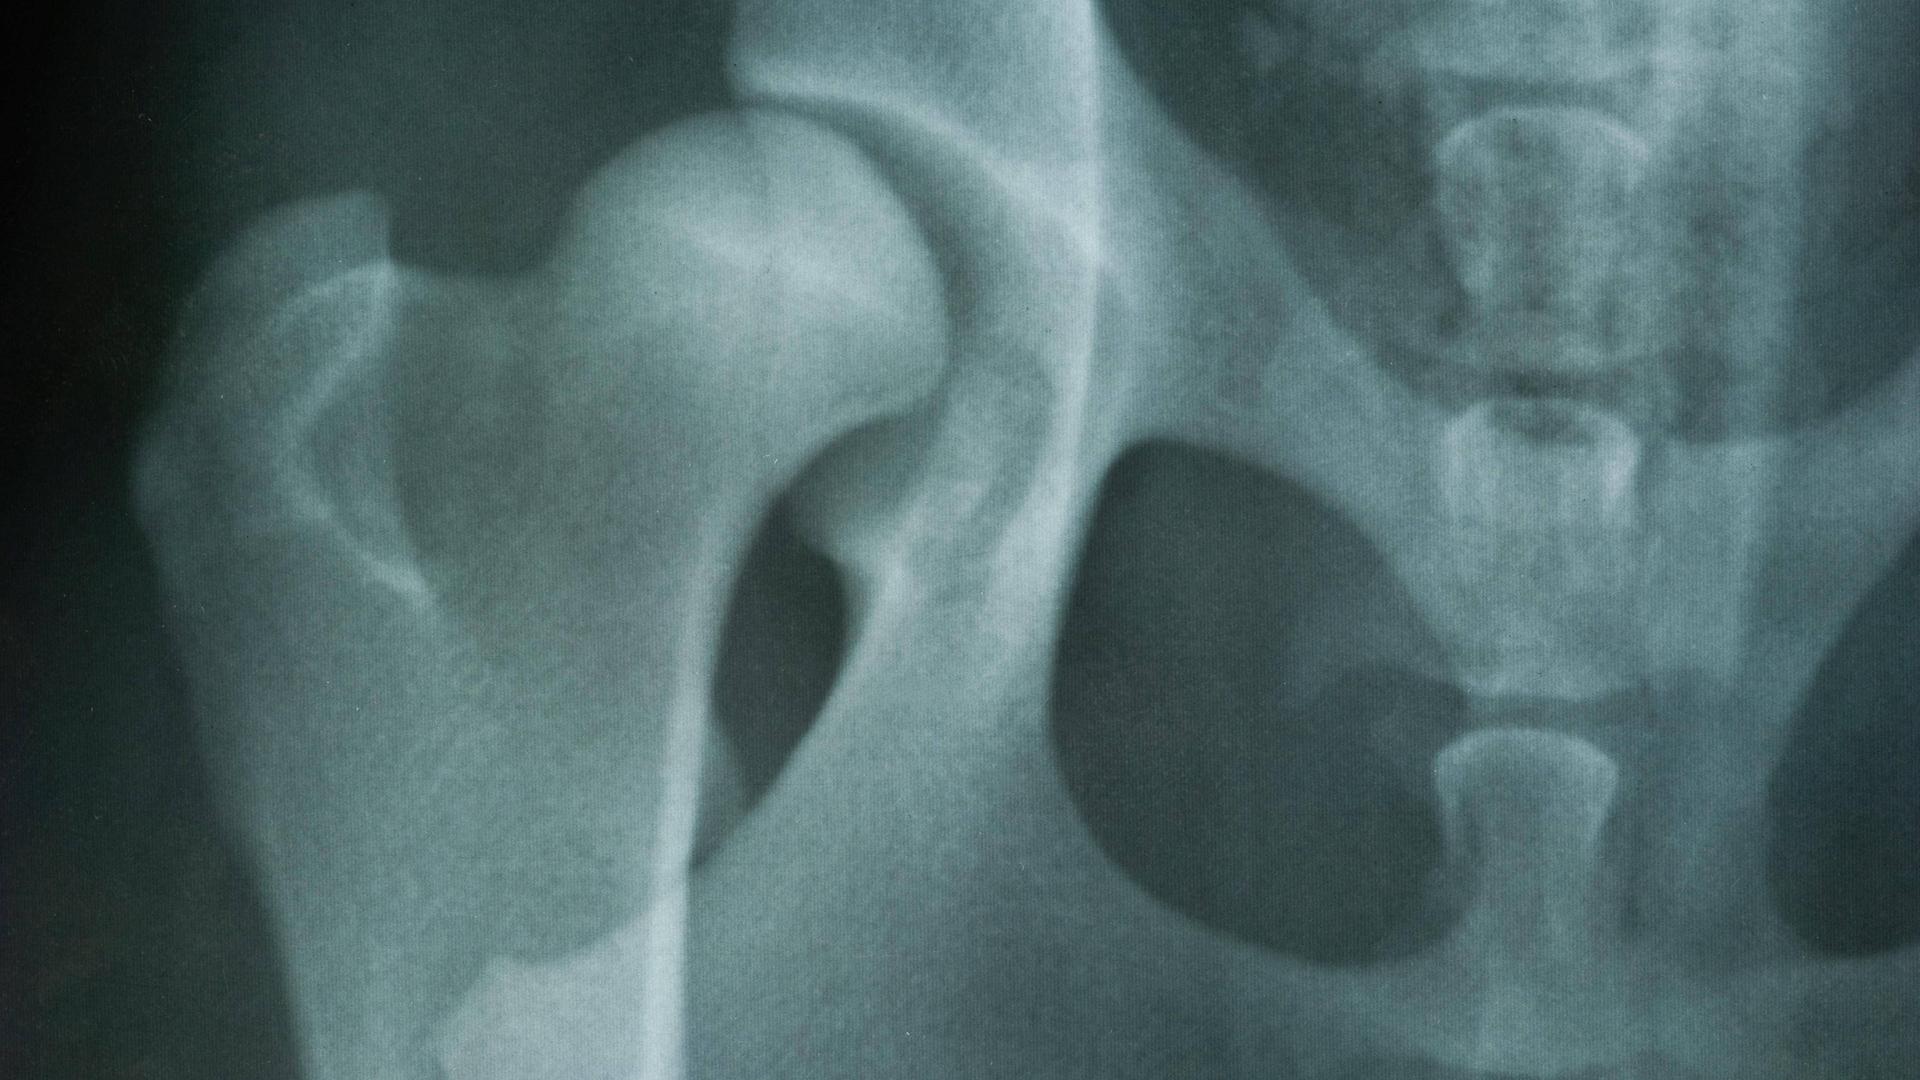

Hüftgelenksdysplasie

:Warum auch Erwachsene betroffen sind

Ständige Schmerzen in der Hüfte und eine eingeschränkte Beweglichkeit können Symptome einer Hüftgelenksdysplasie sein. Wie die Fehlstellung diagnostiziert und behandelt wird.

Röntgenbild einer Hüftgelenkdysplasie